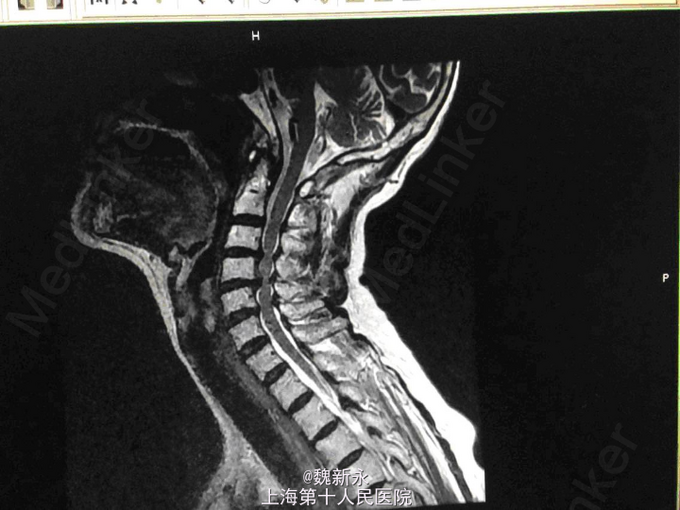

查体:患者精神可,胃纳差,睡眠差,气平,心肺(-),颈部活动僵硬,颈部压痛不明显,双手感觉减退,右侧更重。双侧肱二头肌肌力Ⅴ级,双侧桡侧腕伸肌肌力Ⅳ级,双手握力减退,双侧肱二头肌反射+++,桡骨膜反射+++,双侧肱三头肌反射++,双侧Hoffmen征+,双侧踝阵挛+,双侧Babinski征-,双下肢股四头肌/拇长伸肌/拇长屈肌肌力Ⅳ级,双下肢膝反射/踝反射亢进。 辅检:MRI:颈4-5、颈5-6、颈6-7椎间盘突出,脊髓局部受压,颈椎退变。

诊断:脊髓型颈椎病 治疗经过:患者入院后完善术前检查及准备,在全麻下行颈前路减压植骨融合内固定术,术顺安返,术后予以抗炎、消肿、止痛。营养神经、化痰等对症支持治疗。